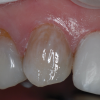

(6.) Pretreatment photograph of an intrinsically stained tooth.

Figure 6

(7.) A pink opaquer was placed prior to the placement of composite.

Figure 7

(8.) Posttreatment photograph of the completed direct composite veneer. (The photographs for the case depicted in Figure 6 through Figure 8 were provided by William “Bud” Mopper, DDS, MS.)

Figure 8

The degree of invasiveness of a composite veneer is dependent on the clinical scenario. In the case of an intrinsically discolored tooth, the tooth may have to be prepared to create room for the restorative materials. By virtue of composite resin's inherent optical properties, it has a limited ability to conceal discoloration. The application of a thin layer of an opaquer (eg, Creative Color® Opaquer and Creative Color® Pink Opaque, Cosmedent; Constic [Opaque-White], DMG; IPS Empress® Direct Opaque, Ivoclar; Estelite Color® [Pink Opaque], Tokuyama) prior to the placement of the composite can provide an alternative to placing a thicker layer of composite and reduce the amount of tooth structure that needs to be prepared. Opaquers are low-viscosity, highly pigmented resins that contain metal oxides. They are ideally suited for cases in which dark tooth structure needs to be blocked out prior to the placement of composite. They come in many colors, including but not limited to pink, white, and tooth colored. By virtue of their opacity, opaquers will raise the value of restorations. On the other hand, if a material that is too translucent is applied, it may appear grey. Opaquers can be applied after the bonding agent is applied and cured. They are often applied in multiple layers, typically with a brush, and cured after each layer is placed. They can also be applied between layers of composite. Clinicians should consult the manufacturer's recommendations to determine the layering technique of their chosen opaquer. However, as aforementioned, excessive application of opaquer may result in a tooth that is of considerably higher value or far more opaque than its adjacent teeth. Once the desired amount of opaquer has been placed, composite is then placed as the final restorative layer (Figure 6 through Figure 8).